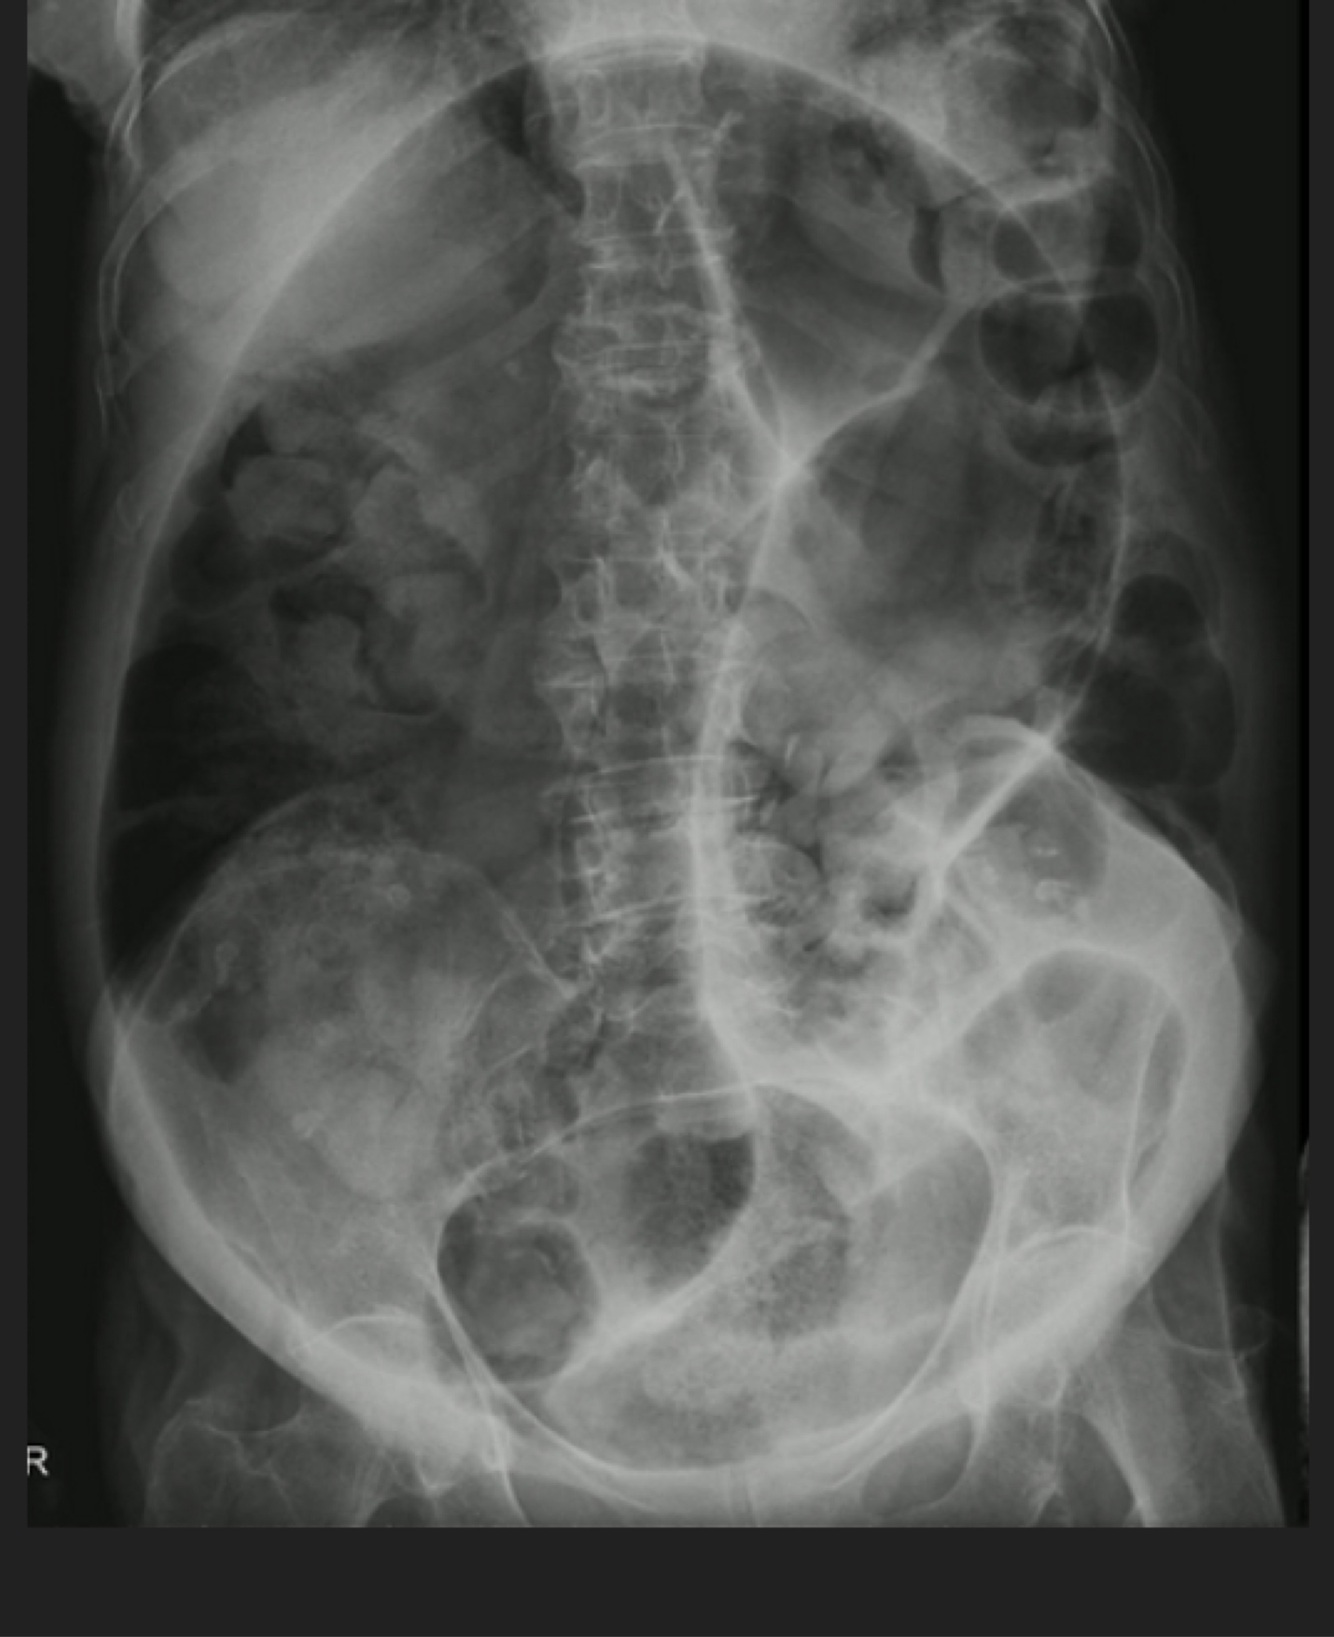

Paciente masculino de 73 años de edad, dolor abdominal severo, imposibilidad para evacuar y canalizar gases 12 hrs

A

Volvulus

Femenino de 68 años. Dolor abdominal, distensión abdominal, imposibilidad para evacuación y canalización de gases 18 hrs

Oclusión intestinal